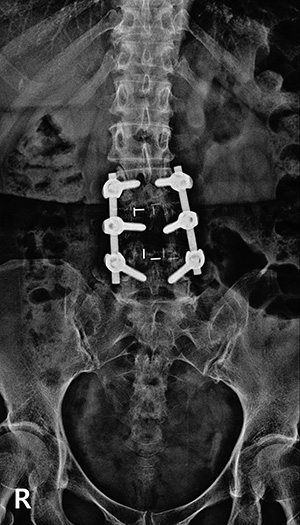

▼ 척추뼈 2개를 묶은 유합술 ▼

• 유합술 전면 X-ray

▼ 척추뼈 3개를 묶은 유합술 ▼